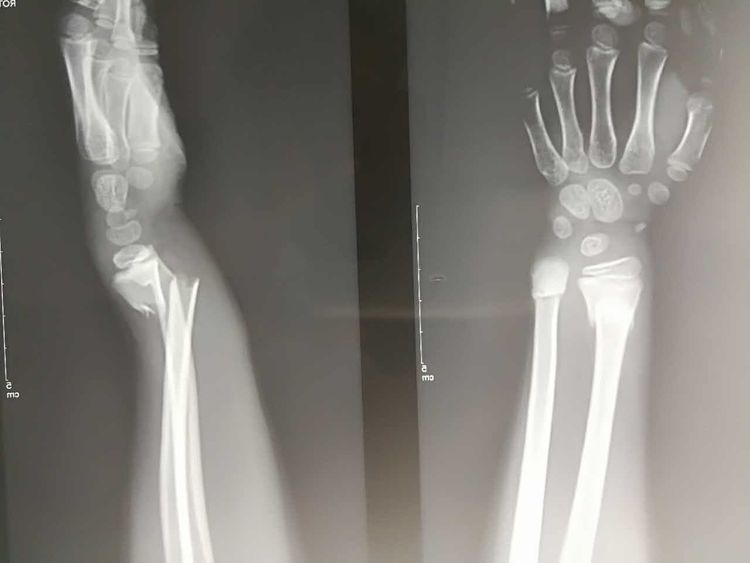

尺桡骨远端骨折指尺桡骨远端2-3cm范围内,常伴有桡腕关节及下尺桡关节的损坏,可出现腕部肿胀、压痛明显,手和腕部活动受限。X线检查可见有清晰的骨折线。

尺桡骨远端骨折治疗以保证腕关节的稳定性,帮助回归正常生活以及避免后遗症等为目的,可遵医嘱给予手法复位外固定治疗,若骨折严重或非手术治疗无效,则需考虑手术治疗,以促进恢复。